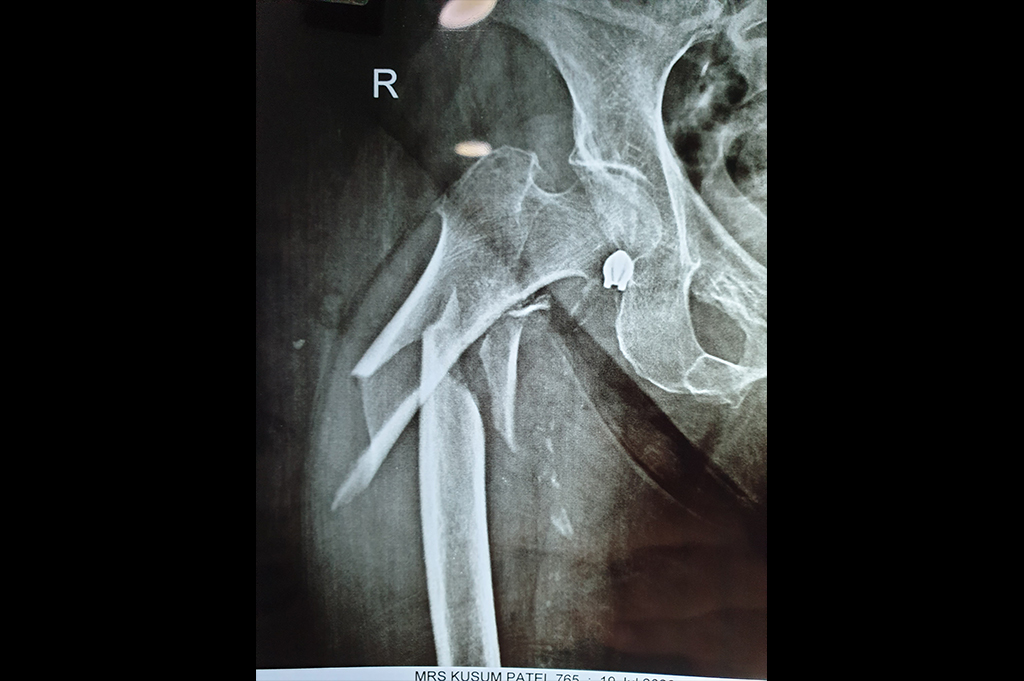

Intertrochanteric Fracture